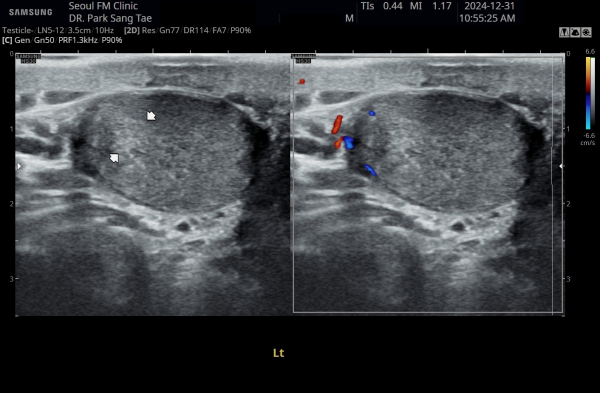

약 8개월 전 전립선과 전립선관,사정관,사정관입구,정낭 그리고 정관의 표적 치료전 좌측 정관과 고환의 순환장애로

고환의 섬유화가 관찰되는 초음파 사진입니다.

This ultrasound image, taken about 8 months ago before starting targeted treatment of the prostate, prostatic ducts, ejaculatory ducts, seminal vesicles, and vas deferens, shows poor circulation in the left testicle. Due to this circulation problem, some fibrosis (scarring) of the testicle can be observed.